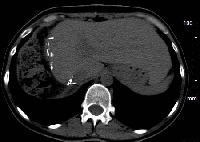

Πρόκειται για γυναίκα ασθενή 32 ετών, η οποία υποβλήθηκε σε αξονική τομογραφία για άτυπα γαστρεντερικά συμπτώματα και άνοδο των ηπατικών ενζύμων. Διαπιστώθηκε συμπαγής μάζα του ήπατος, η οποία εντοπίζονταν τόσο στο δεξιό (τμήματα 5 και 8) όσο και στον αριστερό (τμήμα 4) λοβό. Η ηπατική ογκομέτρηση ανέδειξε ότι τα τμήματα 1, 2 και 3 αποτελούσαν το 30% του συνολικού όγκου του οργάνου (εικόνες 1, 2). Υποβλήθηκε σε δεξιά εκτεταμμένη ηπατεκτομή (εικόνα 3). Στο παρασκεύασμα φαίνεται η μάζα. To μέγεθός της ανέρχεται σε 8 εκατοστά (εικόνα 4). Σε οβελιαία τομή, διακρίνεται η χαρακτηριστική κεντρική ουλή της εστιακής οζώδους υπερπλασίας (εικόνα 5). Ο σχετικός όγκος του υπολοιπόμενου ήπατος ανήλθε στο 64%, ένα μήνα μετά την ηπατεκτομή (εικόνα 6). Η ασθενής είναι ελεύθερη συμπτωμάτων.